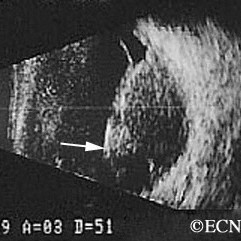

Choroidal melanoma

Choroidal melanoma- Dome shaped with retinal detachment. Low internal reflectivity seen on interpolated A-scan (arrow).